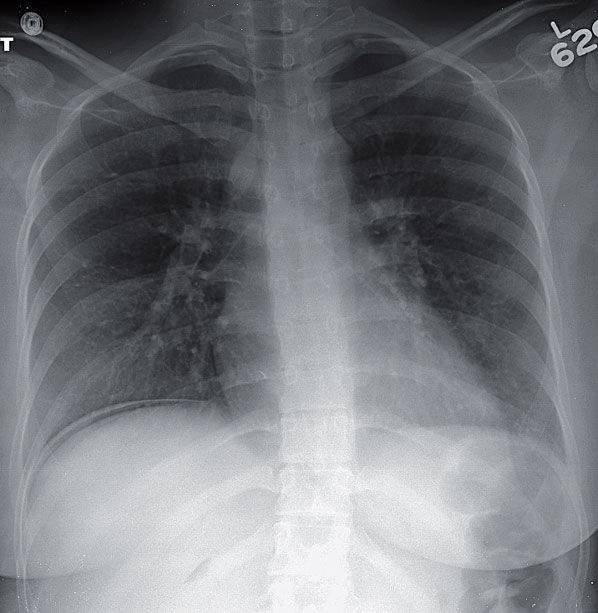

26-year-old Woman With Sudden Onset of Chest and Shoulder Pain Post category:Spot Diagnosis Post published:January 25, 2026 Share on Facebook Share on X (Twitter) Share on Pinterest Share on Email Share on Reddit 26-year-old woman with sudden onset of chest and shoulder pain 26-year-old woman presents with sudden onset of chest and shoulder pain. What’s the diagnosis ? FULL CASE AND ANSWER Share on Facebook Share on X (Twitter) Share on Pinterest Share on Email Share on Reddit Read more articles Previous Post22-year-old Man With Severe Sudden Onset of Chest Pain Next PostPink Plaques in a Healthy Infant You Might Also Like 2-year history of a nonhealing ulceration on the left heel June 27, 2022 A 74-year-old Woman With Lower Abdominal Pain, Nausea and Vomiting August 26, 2022 Patient with Cough, Congestion, Chest and Abdominal Pain September 18, 2022